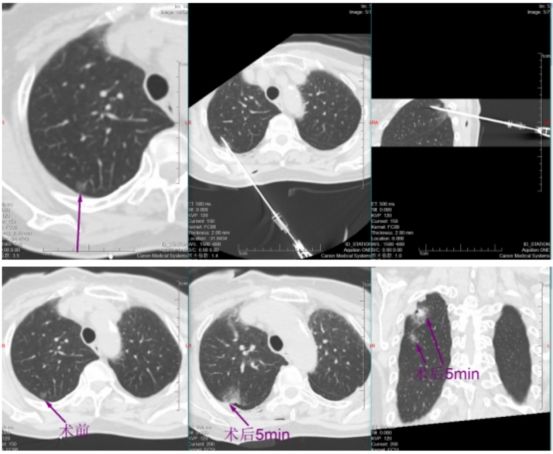

挑战随即开始。帕金森病导致黄女士身体不时微颤,这对需要毫米级稳定的穿刺是巨大干扰。于明川凝神屏息,双手稳如磐石,细微调整针道,在CT的实时引导下,消融针稳稳穿过8毫米的磨玻璃结节,精准停在胸膜前方3厘米处,完美避开胸膜危险区。“开始消融,30瓦一分钟!”随着指令下达,微波消融针开始加热,热量在结节处缓缓扩散,将病灶逐步凝固坏死。黄女士全程清醒,未感丝毫不适。

一分钟后,复查CT显示,结节被一圈磨玻璃密度影完整包裹,这意味着病灶已完全处于烧灼区内,第一枚结节消融成功!

稍后,于明川与冯文汉等团队成员密切配合,向难度更高的第二枚结节发起冲击。这枚结节藏在叶间裂与胸膜构成的狭小夹角内,可操作空间极小,如同在“夹缝中绣花”。按照术前预案,于明川放弃平行进针思路,采用由下而上的特殊进针方式,巧妙避开关键解剖结构。针尖精准抵达结节区域,经过反复测量确认安全后,30瓦功率持续消融一分钟。术中,黄女士的心率、血压始终平稳,未出现任何不良反应。术后CT扫描证实,结节被完全覆盖,烧灼区与叶间裂仅隔几毫米,这毫厘之间的精准,正是生命安全的坚实屏障。

一小时后,铅门再次打开。于明川将黄女士的儿女引至屏幕前,影像清晰地显示:两枚结节已被完全覆盖,消融范围边缘距离关键解剖结构仅有毫厘之差。“两个结节都顺利消融成功了,没有并发症,手术很成功!” 话音落下,黄女士儿女心中悬了许久的大石终于落地。看着术后安然躺在病床上、面容平和的母亲,他们眼中盈满欣慰。